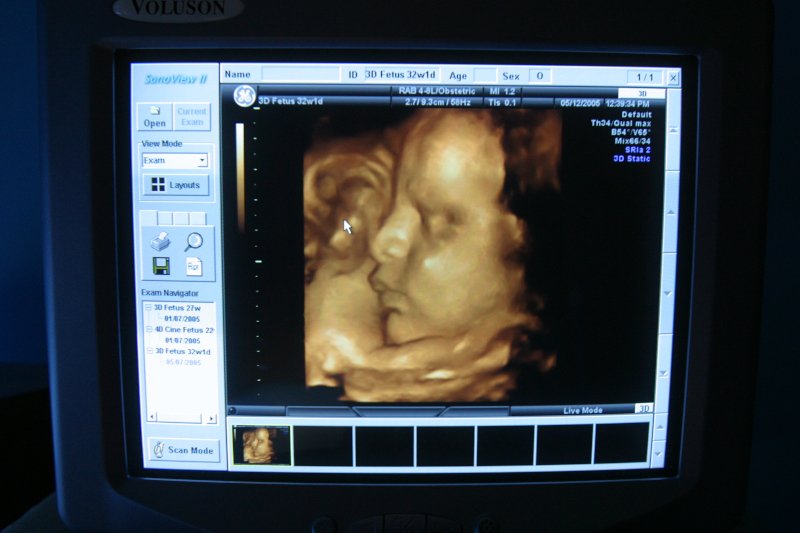

– Z punktu widzenia medycznego każda pacjentka, która jest w ciąży, powinna mieć takie badanie wykonane – zaznacza w rozmowie z naTemat ginekolożka dr Anna Parzyńska, która podpowiada, na co kobiety powinny zwracać szczególną uwagę, gdy mowa o badaniach prenatalnych.

Coś takiego nie wchodzi w grę. Zgodnie z wytycznymi Polskiego Towarzystwa Ultrasonograficznego i Polskiego Towarzystwa Ginekologów i Położników mamy obowiązek, jako lekarze, wykonywać trzy podstawowe badania w ciąży – badanie I, II i III trymestru.

One nazywają się badaniami prenatalnymi z tej prostej przyczyny, że wykonuje się je w okresie prenatalnym, czyli w ciąży. Badania prenatalne są dla pewnych grup osób refundowane. Żeby mieć je zrobione na NFZ – bezpłatnie, trzeba mieć do takich badań wskazania.

Jednak z punktu widzenia medycznego każda pacjentka, która jest w ciąży, powinna mieć takie badanie wykonane. Jeżeli prowadzi ciąże prywatnie bądź na NFZ, ale nie ma wskazań do ich wykonania, to lekarz i tak powinien o istocie tych badaniach poinformować.

Pierwsze badanie miedzy 11 a 13 tygodniem ciąży plus 6 dni. Drugie między 18 a 22 drugim tygodniem. Zachęcam, żeby robić do 20 tygodnia, ponieważ do 22-24 tygodnia mamy czas na zakończenie ciąży z uwagi na nieprawidłowości.

Jeśli mówimy o badaniach pierwszego trymestru, to ważne są dwie rzeczy. Pierwsza –czas trwania ciąży, ponieważ można je zrobić tylko w określonych widełkach czasowych. Bardziej nas interesuje długość płodu, musi wynosić między 45 a 84 mm, gdy chcemy to badanie wykonać. W przeciwnym razie program nie policzy nam ryzyka. Nie ma badan na płodach powyżej i poniżej tych wartości.

Lekarz, który wykonuje badania prenatalne powinien posiadać certyfikaty Fundacji Medycyny Płodowej, która znajduje się w Londynie. Jestem bardzo za tym, żeby miał wszystkie certyfikaty, czyli żeby miał certyfikat na przezierność karkową, na kość nosową, na przepływ przez zastawkę trójdzielną i w przewodzie żylnym.

Zawsze zachęcam do tego, żeby pacjentki dostawały zdjęcia, bo to jest ich własność. Mają prawo do takiej obrazowej dokumentacji. Lekarz, który wykonuje badanie powinien omówić wynik tego badania z pacjentką, poinformować ją do jakiej grupy ryzyka ją to kwalifikuje.